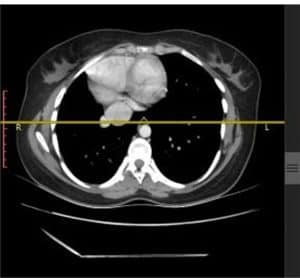

Investigations: Initial chest radiography revealed right lung volume loss and ipsilateral mediastinal displacement, raising suspicion for venous anomalies (Figure 1). A contrast-enhanced chest computed tomography (CT) scan was then performed, confirming the diagnosis of scimitar syndrome. The imaging demonstrated an anomalous right pulmonary vein draining into the IVC, associated with hypoplasia of the right lung (Figure 2, Figure 3, Figure 4). Additionally, two-dimensional transthoracic echocardiography was conducted to evaluate for any associated cardiac anomalies, which were not detected. An abdominal ultrasound was performed to assess liver size and anatomical relationships, yielding unremarkable results.

Figure 4: Chest CT

Showing the lower part of the aberrant venous drainage into IVC (arrowhead PV, arrow IVC).